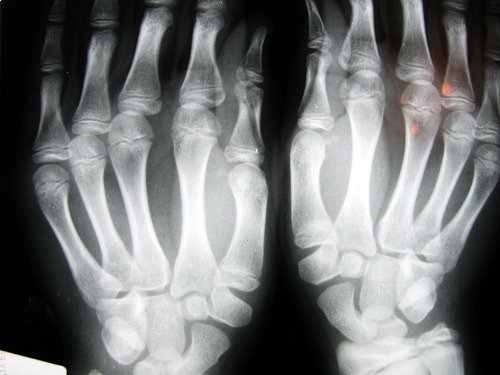

2. Osteoartrit Riski

Nottingham Üniversitesi (Birleşik Krallık) tarafından yapılan bir araştırmada daha kısa işaret parmağına sahip insanların osteoartrit gibi problemlere sahip olma riskinin daha fazla olduğu görülmüştür.

Bu, düşük östrojen ve az fiziksel aktivite ile bağdaştırılırken, genellikle kadınları etkiler.